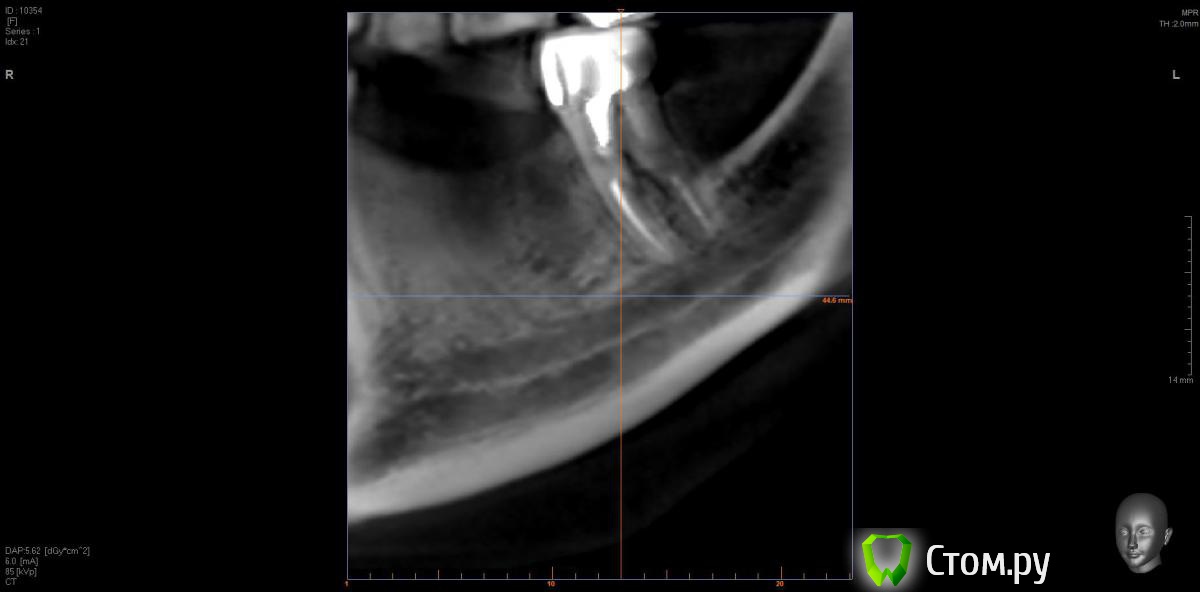

Opimar Опубликовано 21 июня, 2014 Автор Поделиться Опубликовано 21 июня, 2014 Выкладываю еще. Пошагово от 34-37 Ссылка на комментарий

Bier Опубликовано 21 июня, 2014 Поделиться Опубликовано 21 июня, 2014 Выкладываю еще. Пошагово от 34-37темная точка достаточно высоко, это по моему не нерв, нерв ниже, я правильно понимаю? Ссылка на комментарий

Opimar Опубликовано 21 июня, 2014 Автор Поделиться Опубликовано 21 июня, 2014 темная точка достаточно высоко, это по моему не нерв, нерв ниже, я правильно понимаю?Да он ниже и язычнее. Провел от менталиса там еще запас есть. Ссылка на комментарий